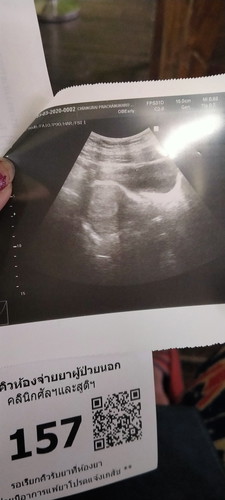

ตรวจว่าท้องแต่พอไปซาวค์ไม่เจอน้องแบบมีสิทธท้องมัยค่ะ

อยากรู้ว่าจะท้องมัยค่ะ

บ้านนี้ ตอนท้อง 5 w ซาวหน้าท้องไม่เจอค่ะ เลยซาวทางช่องคลอด เจอน้องค่ะ ❤️

อายุครรภ์ยังน้อยอยู่รึป่าวคะ บางทีถุงตั้งครรภ์อาจจะยังเล็กมาก

ถ้าท้องอ่อนๆไม่เจอค่ะแม้แต่ถุงก็ยังไม่เจอของเรามาเจอถุงช่วง7w

เราเจอน้องพร้อมหัวใจตอน 8 วีคค่ะ ก่อนหน้านั้นเจอแต่ถุงเปล่าๆ

ครรภ์ยังเล็ก รออีก1-2อาทิตย์ซาวใหม่จ้าบ้านนี้เจอน้องตอน8week